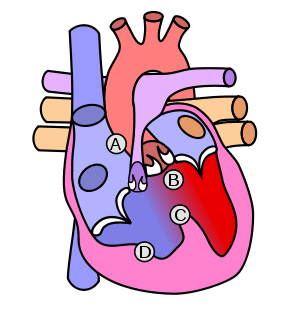

| Diagram of a healthy heart and one with tetralogy of Fallot | |

The cause is typically not known. Risk factors include a mother who uses alcohol, has diabetes, is over the age of 40, or gets rubella during pregnancy. It may also be associated with Down syndrome.[4] Classically there are four defects:[2]

- a ventricular septal defect, a hole between the two ventricles

- pulmonary stenosis, narrowing of the exit from the right ventricle

- right ventricular hypertrophy, enlargement of the right ventricle

- an overriding aorta, which allows blood from both ventricles to enter the aorta

As such, by definition, tetralogy of Fallot involves four heart malformations which present together:

| Pulmonary Infundibular Stenosis | A narrowing of the right ventricular outflow tract. It can occur at the pulmonary valve (valvular stenosis) or just below the pulmonary valve (infundibular stenosis). Infundibular pulmonic stenosis is mostly caused by overgrowth of the heart muscle wall (hypertrophy of the septoparietal trabeculae),[15] however the events leading to the formation of the overriding aorta are also believed to be a cause. The pulmonic stenosis is the major cause of the malformations, with the other associated malformations acting as compensatory mechanisms to the pulmonic stenosis.[16] The degree of stenosis varies between individuals with TOF, and is the primary determinant of symptoms and severity. This malformation is infrequently described as sub-pulmonary stenosis or subpulmonary obstruction.[17] |

| Overriding aorta | An aortic valve with biventricular connection, that is, it is situated above the ventricular septal defect and connected to both the right and the left ventricle. The degree to which the aorta is attached to the right ventricle is referred to as its degree of "override." The aortic root can be displaced toward the front (anteriorly) or directly above the septal defect, but it is always abnormally located to the right of the root of the pulmonary artery. The degree of override is extremely variable, with 5-95% of the valve being connected to the right ventricle.[15] |

| Ventricular septal defect (VSD) | A hole between the two bottom chambers (ventricles) of the heart. The defect is centered around the most superior aspect of the ventricular septum (the outlet septum), and in the majority of cases is single and large. In some cases thickening of the septum (septal hypertrophy) can narrow the margins of the defect.[15] |

| Right ventricular hypertrophy | The right ventricle is more muscular than normal, causing a characteristic boot-shaped (coeur-en-sabot) appearance as seen by chest X-ray. Due to the misarrangement of the external ventricular septum, the right ventricular wall increases in size to deal with the increased obstruction to the right outflow tract. This feature is now generally agreed to be a secondary anomaly, as the level of hypertrophy tends to increase with age.[18] |